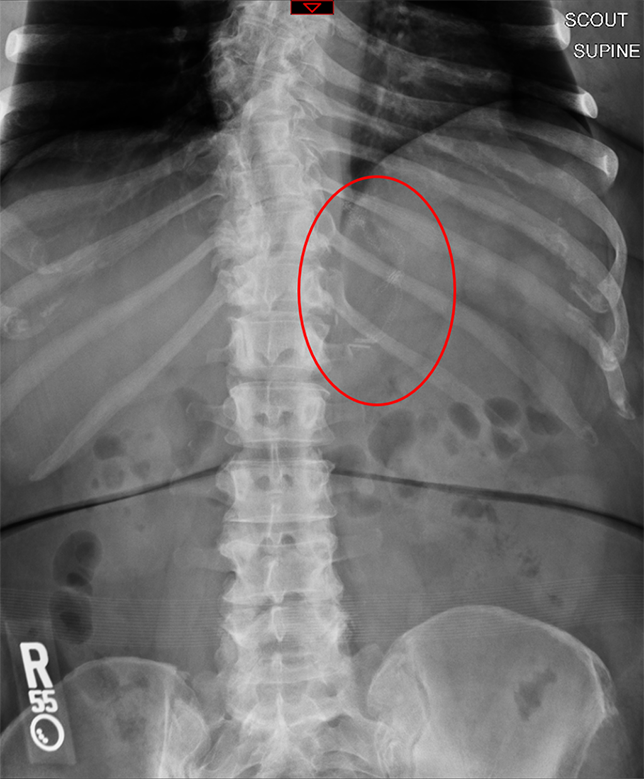

- The technologist will obtain a scout image. Assess the image for any possible contraindications such as pneumoperitoneum, evidence of ileus or obstruction, or residual contrast material

(key image 1).